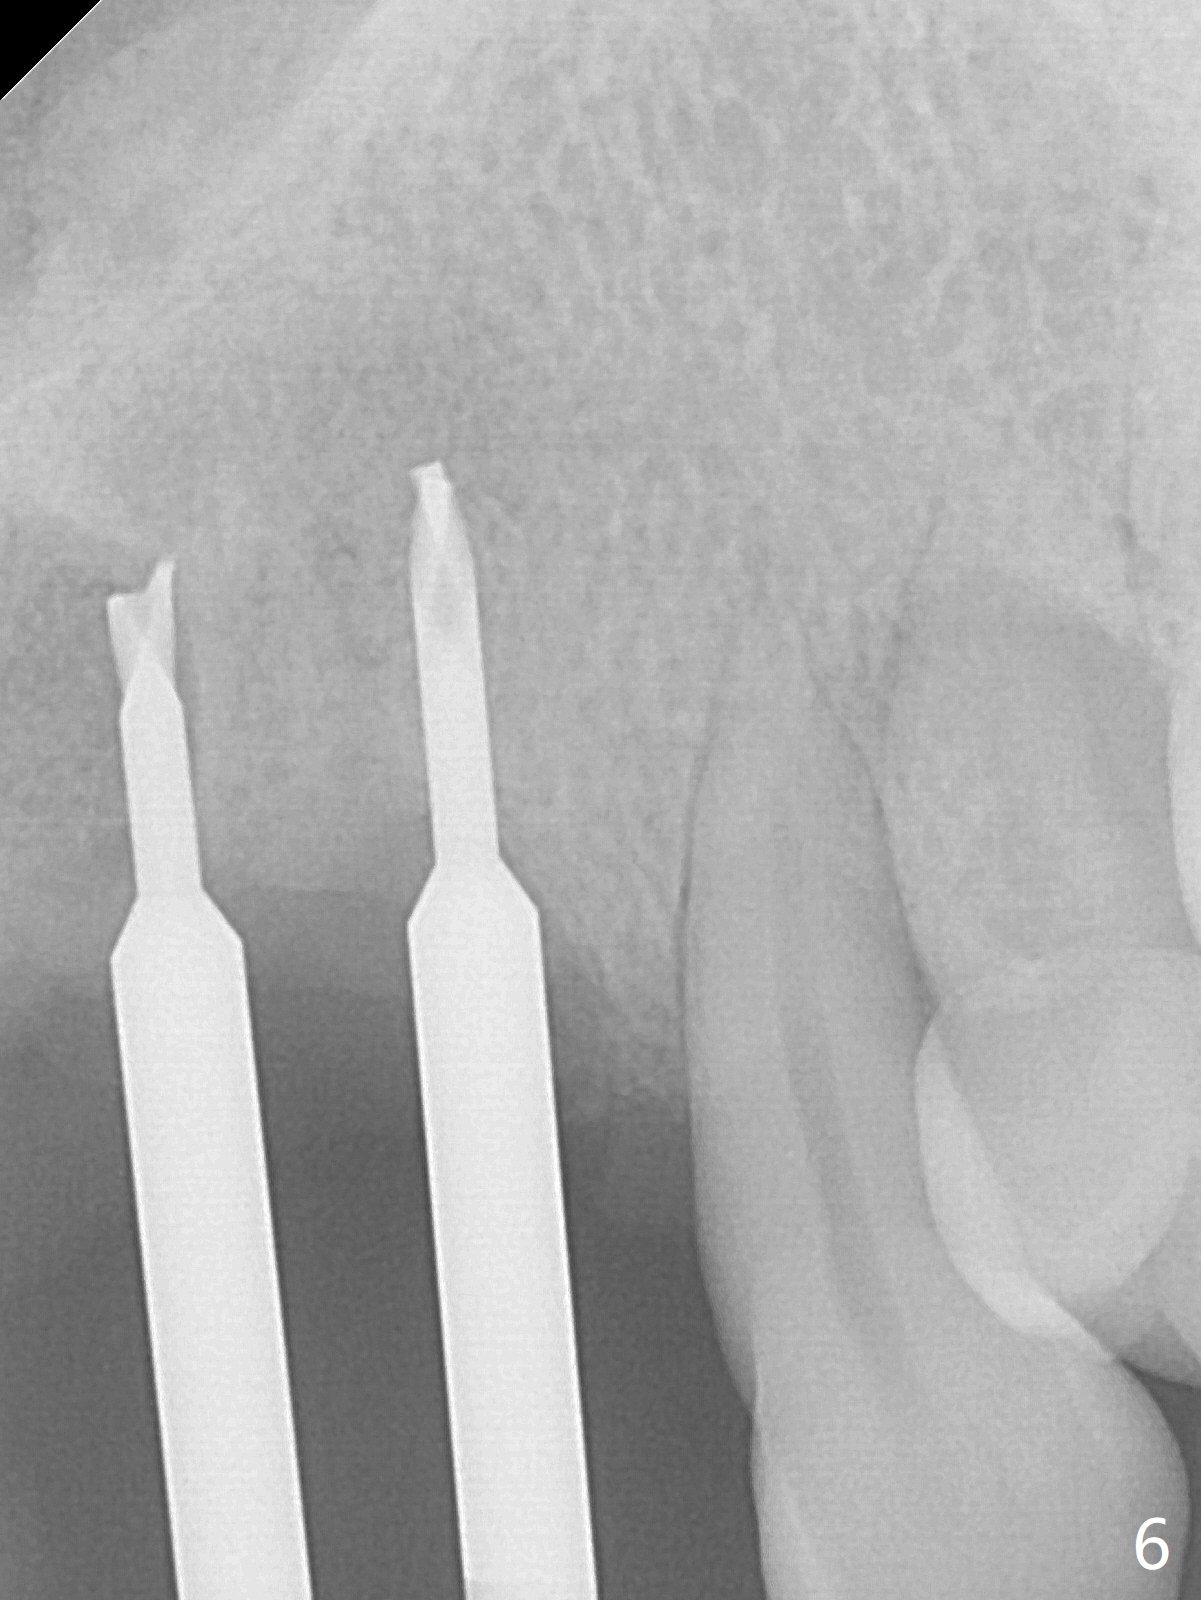

Although the ridge of the maxillary anterior ridge looks moderate in width (Fig.1), the bone is ~4 mm buccopalatally. Suction down surgical stent (Fig.2') made from the lab-fabricated provisional (Fig.2) will be used to check the position and trajectory of osteotomies. PAs taken after initial osteotomies (1.2 mm drill) show those at the central incisors tend to be mesial (close to the Incisive Canal *), while those at the lateral incisor sites distal (Fig.3,4). After adjustment, the position and trajectory of the osteotomies are acceptable (Fig.5,6). To reduce the chance of perforating the Incisive Canal (Fig.3,4 *), 2.5 mm 1-piece implants are inserted with >40 Ncm (Fig.7,8). After deep placement of the implants, Vanilla graft is placed at the crest (Fig.9,10 *). An immediate splinted provisional is fabricated from the suction down stent. The gingiva is healthy around the provisional (Fig.11) and the implants (Fig.12,13) 1 month postop. The provisional is adjusted monthly so that the interdental papillae can be elongated. No bone resorption is observed 6 months postop (Fig.14,15). Crowns are cemented 8 months postop (Fig.16-18). The keratinized gingiva appears to have formed the abutments 8 months postop immediately pre-cementation (Fig.19).